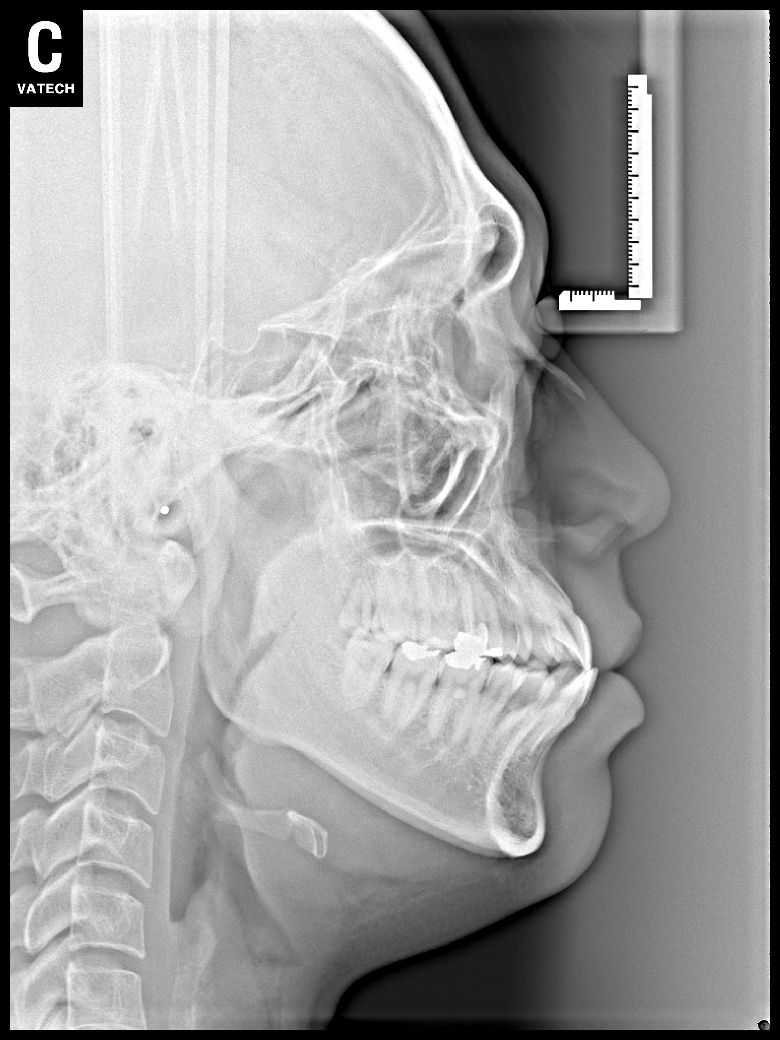

치료 전 사진입니다.